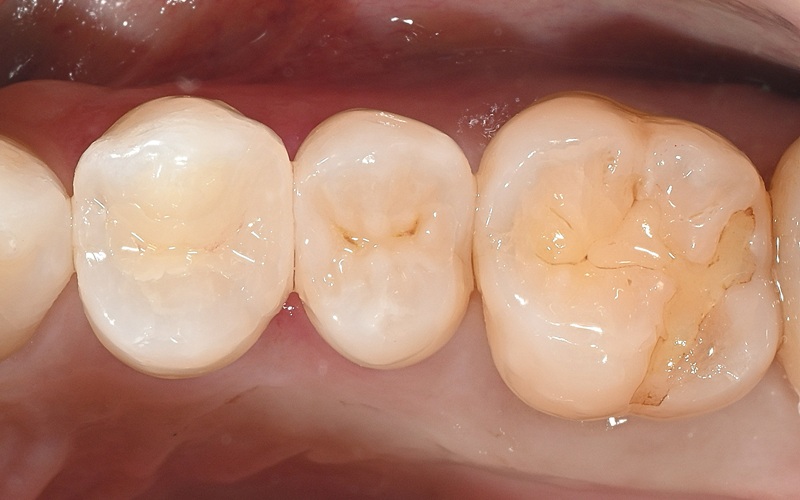

Case4

術前

術中

術後

| 治療名 | ダイレクトボンディング・セラミックインレー |

|---|---|

| 治療説明 | 以前他院で行ったハイブリッドセラミックインレーが劣化したためセラミックインレーとダイレクトボンディングで再修復を行いました。 |

| 治療回数・期間 | 2回 |

| 副作用とリスク | 一時的に知覚過敏が生じることがあります。セラミックとレジンが破折し、再修復が必要になる可能性があります。 |

| 料金(税込) | セラミックインレー:77,000円 ダイレクトボンディング:55,000円 合計:132,000円 |